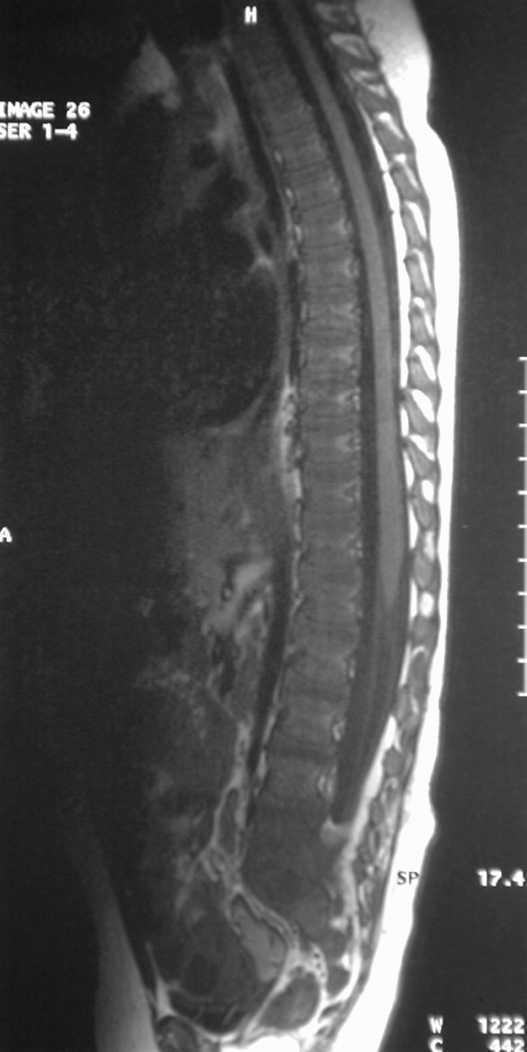

La resonancia magnética (RM) ayuda a diferenciar entre alteraciones óseas vertebrales y patología de la cadera o de la médula espinal. En nuestro caso las imágenes en T1 (fig. 3) con contraste con gadolinio demostraron un realce anormal del disco y de las partes adyacentes de los cuerpos vertebrales y las imágenes en T2 (fig. 4) mostraron una señal anormal y disminución de la altura del disco y unos platillos irregulares, cambios compatibles con espondilodiscitis L5-S1.

Figura 3.RM con gadolinio, se observa realce del disco y cuerpos vertebrales adyacentes entre L5-S1.